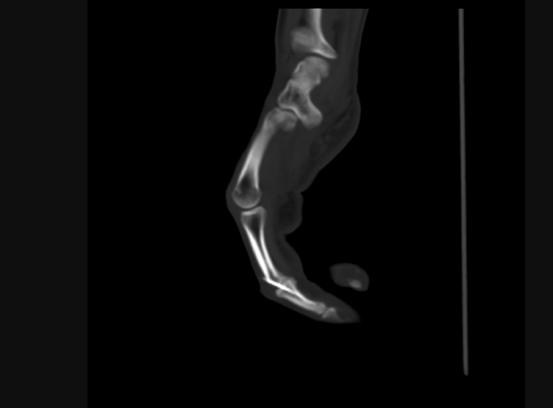

近日,45歲劉先生在工地工作時,由于操作不慎,被圓盤鋸割傷右手,導致右手腫痛、嚴重出血,到我院接受治療,經檢查發現右中指關節缺損。930日,我院手足外科團隊成功為其實施自體小關節移植修復術,在手外傷創傷修復領域邁出重要一步。

“所謂自體關節移植,就是將患者自身的關節進行移植和替換,相比傳統的人工關節置換,該技術具有修復及時、沒有排異反應、治愈效果明顯等優點?!敝鞯夺t生胡明興介紹,經放射醫學科行三維CT精準動靜脈及骨重建,在麻醉科的大力支持下,通過將腳趾關節及附近血管、神經、肌肉進行移植,他們僅用一次手術就為患者完成了手指修復,不需要多次開刀,盡可能保障了患者安全。

目前患者恢復良好,一段時間后,移植的關節便可和原本的關節完全一樣,沒有結構和功能差異。

術后手指關節恢復良好